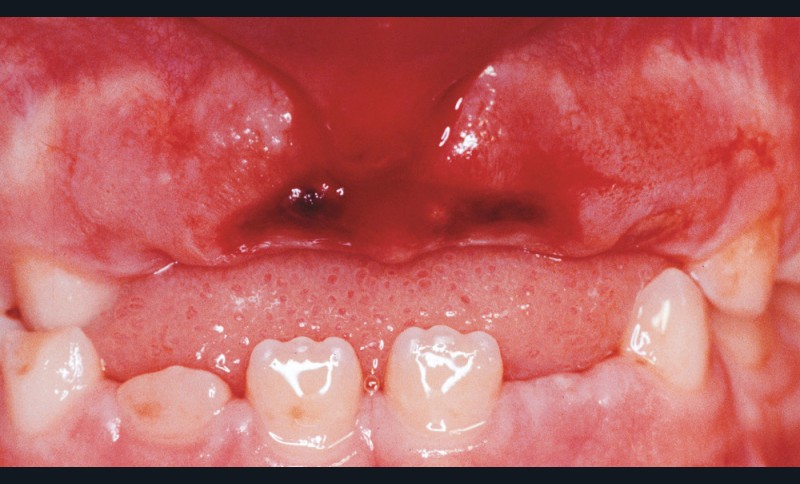

Ils surviennent le plus souvent entre 7 et 10 ans [7], du fait de la laxité du ligament parodontal et de l’immaturité radiculaire (fig. 1).